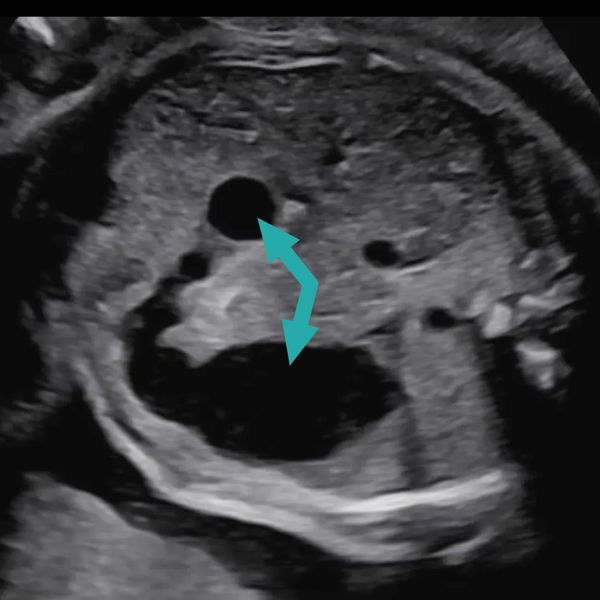

Duodenal atresia is often detected before birth on routine prenatal ultrasound, with the following findings:

(Pic: ultrasound of a fetus with duodenal atresia, with the arrows showing the "double bubble" sign)